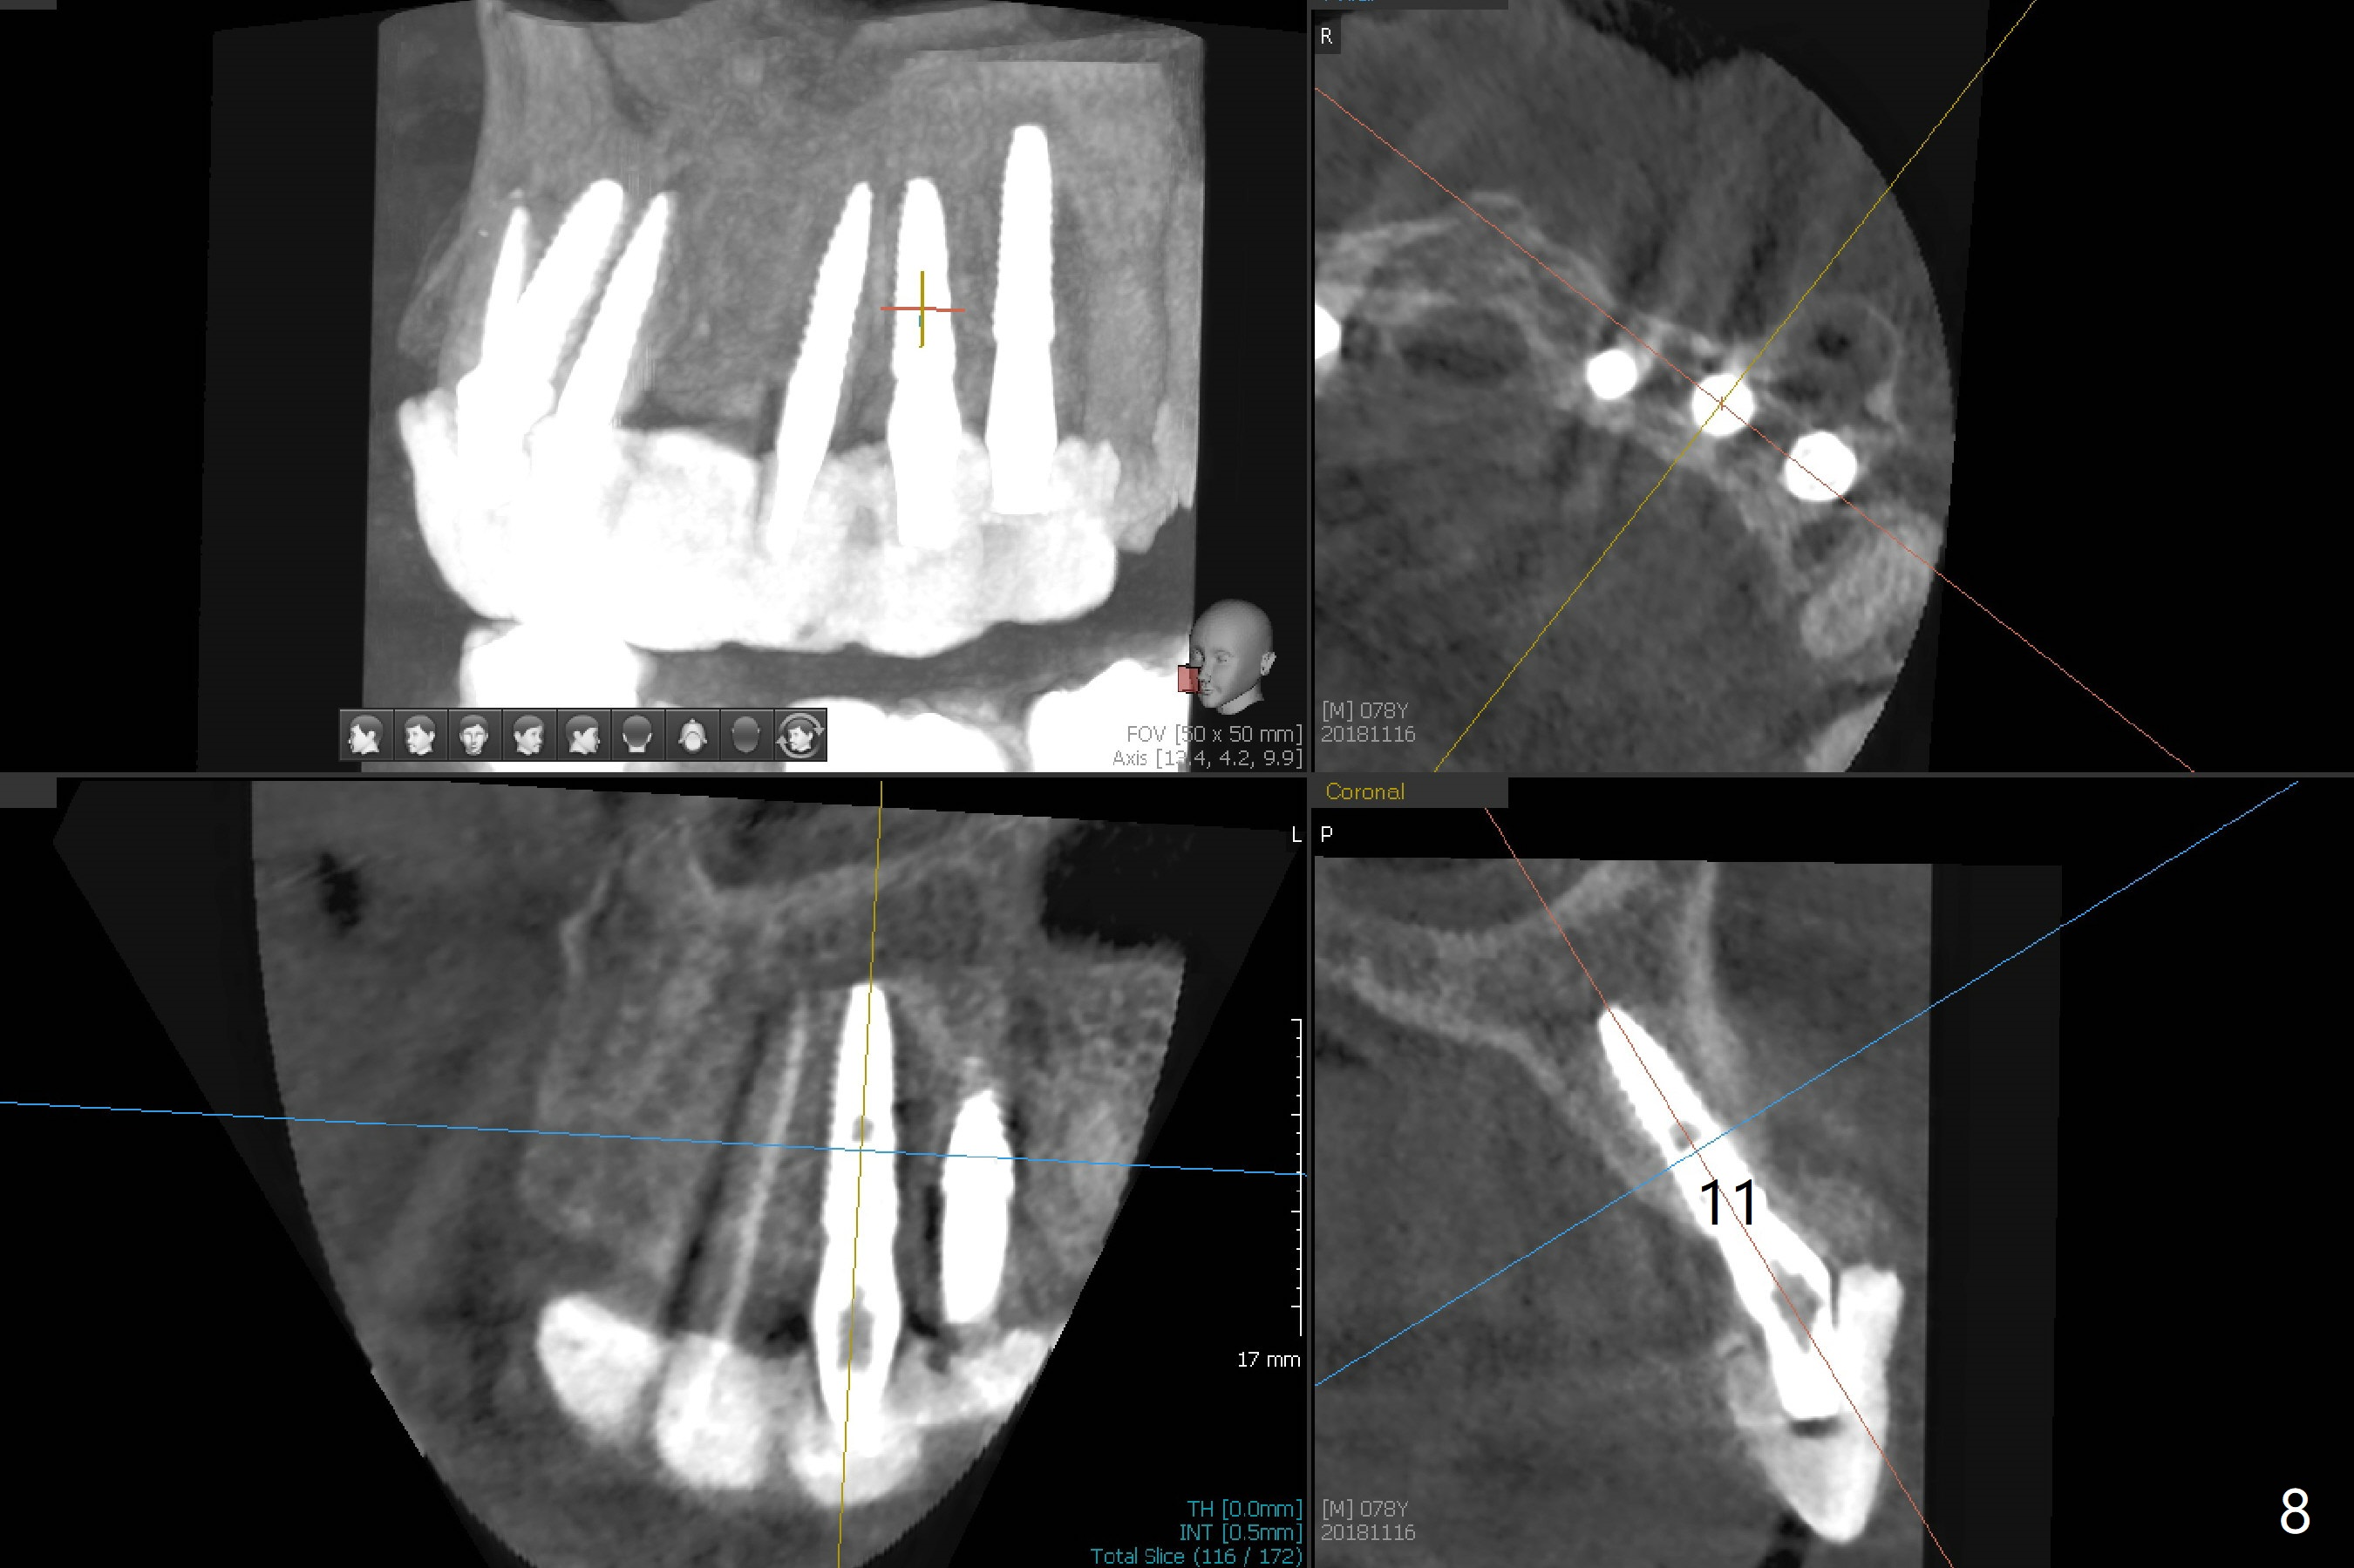

It is smooth and quick to finish osteotomy with guide at #6,7,10-12, but when 3 mm 1-piece implants are placed free hand at #7 and 10 (Fig.1,2), the gingival parts of the abutments contact the incisal edges of the lower incisors (anterior deep bite) in spite of effort to change the trajectory by repeated back and forth placement after use of Lindamann bur buccally. Following an immediate provisional (Fig.3,4), the occlusal surface of the posterior teeth are raised to eliminate anterior restoration interference. Immediate postop CBCT shows that the implants at #7 and 10 could be placed more buccally (Fig.6,7, as compared to the normal position at #6,11,12 (Fig.5,8,9)). Fig.10 was taken 2 days preop, while Fig.11-13 postop. Can we change 1-piece implants (3mm) at #7 and 10 to 2-piece one (3.5) and use angled or cementation abutments for easy restoration (Fig.14-16)?